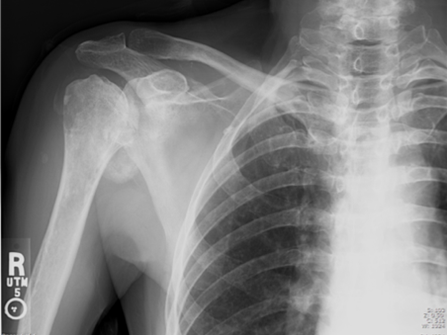

Calcific Bursitis! Hydroxyapatite deposition disease (HADD) is characterized by accumulation of crystals/calcium within articulations and/or in a peri-articular distribution. We commonly see HADD at the rotator cuff tendons, which is usually asymptomatic. However, when shoulder pain is related to the HADD seen on imaging studies, then we make the diagnosis of calcific tendinopathy. In the shoulder we can also see HADD within the subdeltoid/subacromial bursa (calcific bursitis) and within the glenohumeral joint (also known as Milwaukee’s shoulder). A paper published on 1931 argued that “calcific bursitis” was a misnomer, given the belief that the calcium in bursitis isn’t actually deposited in the walls of the bursa but rather shed from the adjacent tendon. Almost 50 years later, the pathophysiology of HADD is still not well understood. Regardless, most radiologists will distinguish the precise location of the Hydroxyapatite deposition, which is easy to determine on imaging studies – tendon > bursa > intra-articular. The treatment and prognosis varies depending on location, so be precise in your dictation! 😉 Also, image guided barbotage of calcific bursitis is usually technically easier than with calcific tendinopathy. #mskrad #mskradiology #radres #radtech #radiologystudent #radiologia #barbotage #calcifictendonitis #hadd #msk🧞♂️